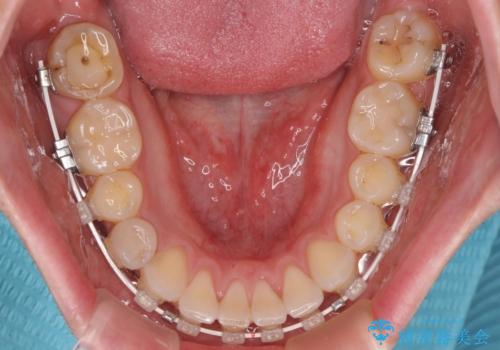

- 矯正装置

- ハーフリンガル

- 治療期間

- 1年4ヶ月

一年と数か月で矯正を終えることができました。